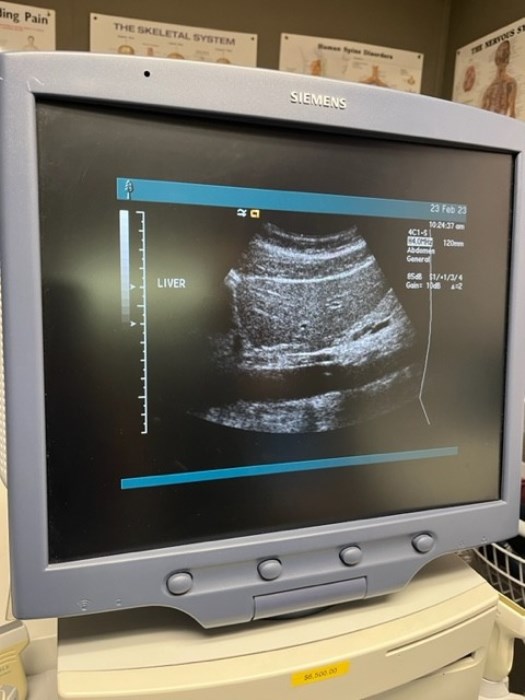

Siemens Sequioa Ultrasound

Pre-owned. In good working condition. Shown as is. Siemens Sequoia Ultrasound. DOM: 2006

Probes: 15L8w, 4V1, 10V4, 6L3, 4C1